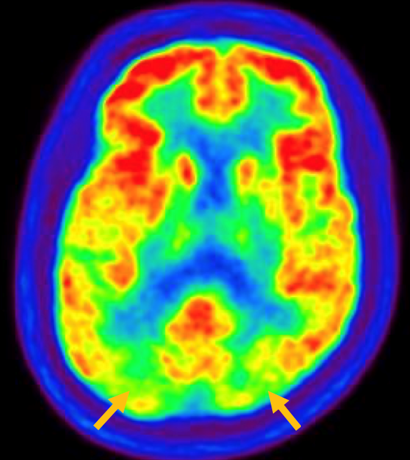

피질 기저핵 변성은 비대칭 증상을 두드러지게 보인다는 점에서 파킨슨병과 비슷합니다. 그러나 파킨슨병과 비교해 보았을 때 양측의 차이가 아주 심하게 나타난다는 특징이 있습니다. 질병 초기에 한쪽 손으로 동작을 하거나 계획된 행동을 하는 기능이 현저하게 떨어집니다. 간단한 손가락 모양도 따라 하지 못하는 현상을 보입니다. 또한 의지와 상관없이 제멋대로 움직이는 통제불능 손이 나타날 수 있습니다. 체위 떨림, 경축, 운동 완만과 같은 파킨슨병에서 볼 수 있는 증상들은 피질 기저핵 변성에서도 관찰될 수 있습니다. 또한 집중력 장애, 수행 장애, 이름 대기나 언어의 유창성이 떨어지는 등 전두엽 및 두정엽과 관련된 인지 장애가 나타납니다. 피질 기저핵 변성은 뇌 자기공명영상(MRI)에서 증상의 반대쪽 전두두정엽의 위축 소견이 특징적으로 나타납니다. 뇌포도당 양전자 단층촬영(PET)에서도 전두엽, 뇌기저핵에 비대칭적인 대사 저하의 소견이 보입니다.

[피질기저핵 변성 환자의 뇌포도당 양전자 단층촬영에서 확인되는 비대칭적인 대사 기능 저하]

루이소체 치매는 파킨슨 증상 발생 초기나 그 이전부터 빠르게 진행되는 인지 기능 저하가 동반되는 질병입니다. 퇴행성 치매의 원인 중 두 번째로 많습니다. 반복되는 환시 증상과 인지, 의식 및 집중력의 변동이 특징적으로 나타납니다. 뇌 자기공명영상(MRI)에서 전반적인 대뇌 위축이 나타나며, 알츠하이머병에 비해 상대적으로 후두엽, 내측 측두엽이 보존되는 모습이 관찰됩니다. 뇌포도당 양전자 단층촬영(PET)을 시행하면 쐐기소엽(cuneus) 및 쐐기앞소엽(precuneus)의 대사가 감소한 상태가 확인됩니다. 그러나 뒤띠이랑(posterior cingulate gyrus)은 상대적으로 보존된 모습을 볼 수 있습니다.

[루이소체치매 환자의 뇌포도당 양전자 단층촬영에서 확인되는 비대칭적인 대사 기능 저하]